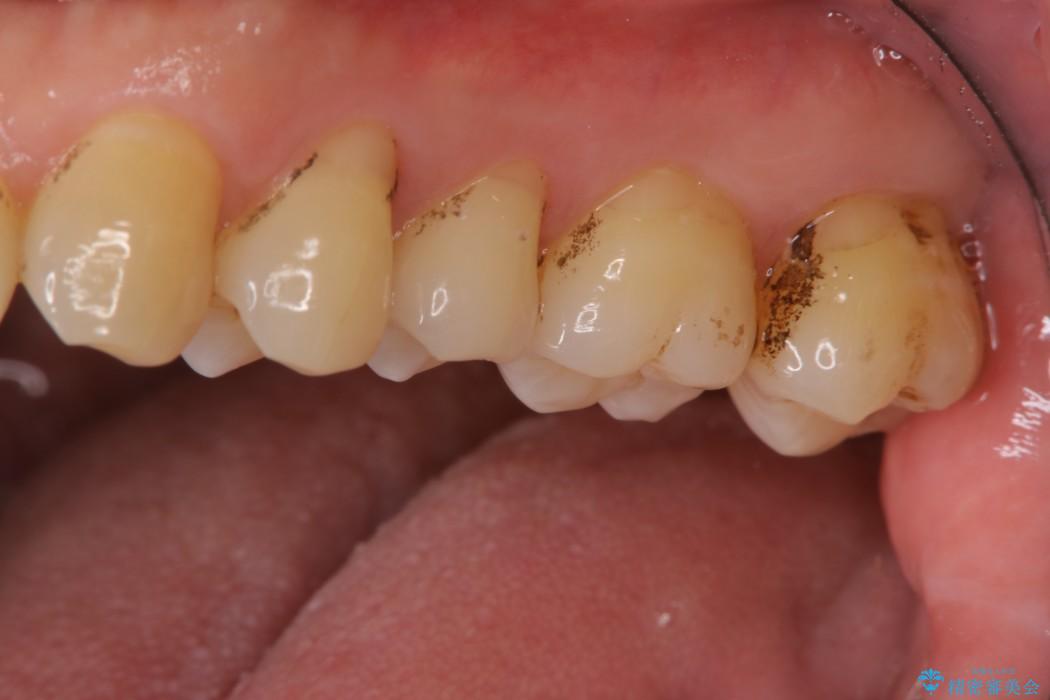

【40代男性】歯にこびりついた着色のクリーニング

普段からコーヒーをよく飲まれる方で、3年間歯医者に行かれておらず、定期健診も込みでご来院されました。

堅くこびりついていたステインも1時間コースのPMTC(プロフェッショナルクリーニング)できれいな状態になりました。